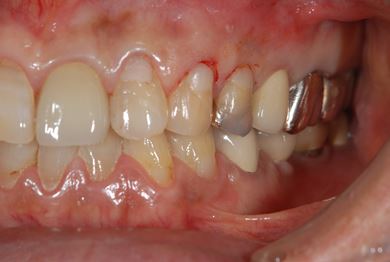

| 性別/年齢 | 男性 / 69歳 | ||||||||||||||||||||||||||||||||

| 主訴 | 1.左上奥歯の詰め物が取れた 2.左上前歯の欠け 3.右下奥歯の欠け | ||||||||||||||||||||||||||||||||

| 治療方針 | セラミック治療にて、審美的回復を行う。 | ||||||||||||||||||||||||||||||||

| 治療内容 | メタルボンドセラミッククラウン1本(メタルボンド用土台1本)、ハイブリッドセラミックインレー1本 | ||||||||||||||||||||||||||||||||

| 総治療費 | 172,410円 | ||||||||||||||||||||||||||||||||

| 治療期間 | 4ヶ月 |